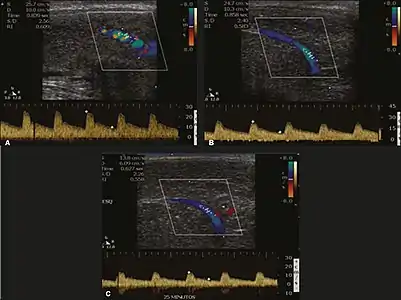

Graphs representing the color Doppler spectrum of the flow pattern of the cavernous arteries during the erection phases. A: Single-phase flow with minimal or absent diastole when the penis is flaccid. B: Increased systolic flow and reverse diastole 25 min after injection of prostaglandin.[44]

Longitudinal, ventral ultrasound of the penis, with pulsed mode and color Doppler. Flow of the cavernous arteries at 5, 15, and 25 min after prostaglandin injection (A, B, and C, respectively). The cavernous artery flow remains below the expected levels (at least 25–35 cm/s), which indicates ED due to arterial insufficiency.[44]